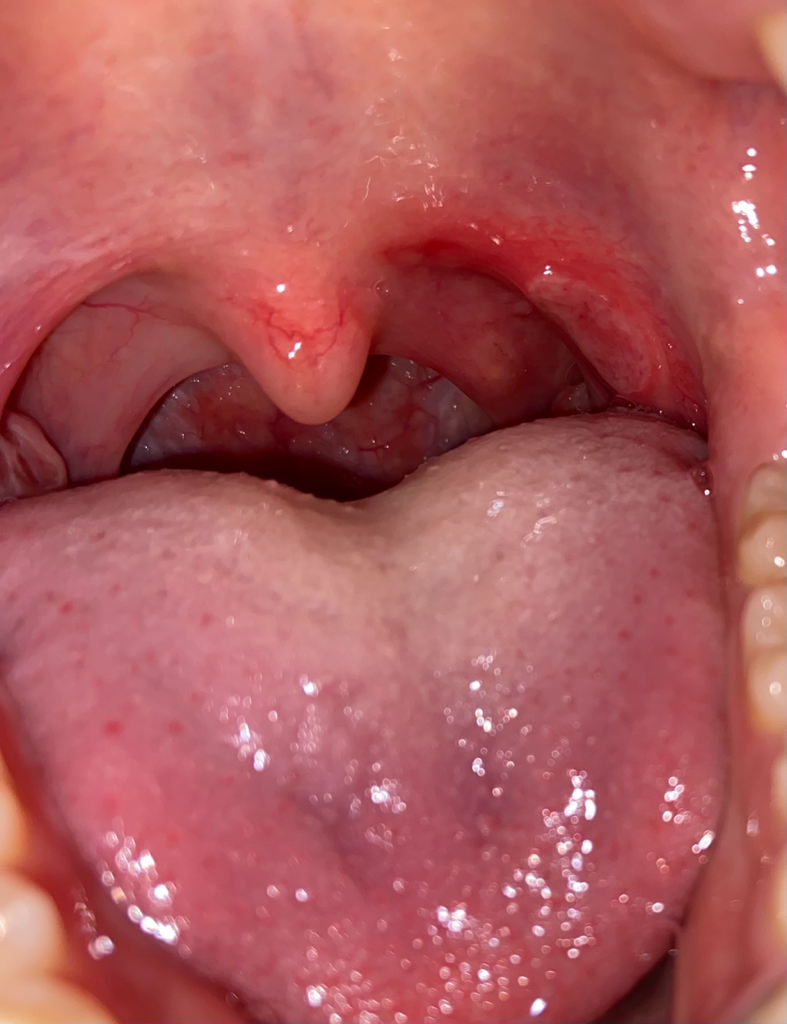

목젖 옆에 구내염? 염증이 있는데 진짜 뒤질듯이 아파요..

구내염 or 편도염

뒤질듯한 고통이 생긴지 3일찬데 점점 더 아파옵니다 ㅠㅠ

병원에서는 감기약만 처방해주던데.. 진짜 밥먹을때 물먹을때는 물론이고 가만히 있어도 살이 타듯이 아파서 머리랑 뒷목, 어깨 근육까지 아파오는 것 같아요.. 하.....

첫번째 사진이 어제고 두번째 사진이 오늘인데 나아질 기미가 안보입니다 왜 상처가 더 커진 것 같죠.. 진짜 미칠것 같아요 고3인데 공부 집중도 안되고 하 돌아버릴것 같네요

소금물 가글도 해봤는데 별 소용 없고.. 병원에서는 딱 편도염이다 구내염이다 정의를 안내려줘서 알보칠도 못바르겠고.. 하.. 어떻게 하면 고통을 줄일 수 있을까요.. 그리고 병원 한 번 더 가봐야될까요? 이비인후과로 갔었는데 어디로 가는게 나은가요?